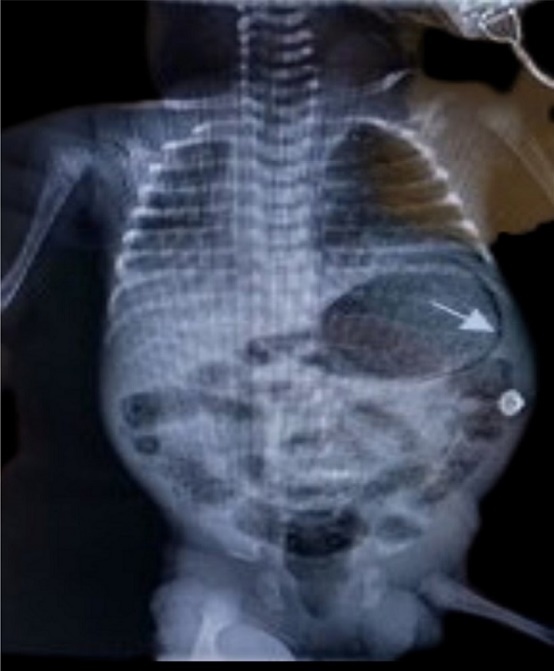

A late preterm (gestational age 35+2/40) male neonate was born to a 25-year-old multiparous woman with minimal antenatal care (5 visits). Her booking parameters were unremarkable and her antenatal period reportedly uneventful. She presented with preterm, prolonged, pre-labour rupture of membranes (PPPROM) and was therefore induced with Cytotec® (Misoprostol); liquor was said to be clear. There were no signs of chorioamnionitis and no antibiotics or steroids were given during delivery. He was delivered via spontaneous vaginal delivery (SVD), and was suctioned; nil other active resuscitation was required. APGARs were 9 and 9 at 1 and 5 minutes respectively. Essential newborn care was offered. Initial examination was unremarkable with temperature of 36.8◦C. He was of low birth weight at 2.46 kg. He was allowed to room in with his mother on the postnatal ward; however by 6 hours of life he was notably distressed characterized by grunting and accessory muscle use, despite a normal respiratory rate of 56. Pre and post ductal saturations were acceptable (97% respectively).Given the presence of danger signs and his history of prematurity on a background of PPPROM, he was admitted to the Neonatal Intensive Care Unit (NICU), nursed in an isolette, attached to cardiac monitor and was screened. Blood and urine culture were taken, complete blood count documented and Chest X-ray (C-XRAY) requested. He was started on ampicillin and gentamycin which are first line antibiotics based on our local protocol. He required mixed gases via nasal cannula on admission and oxygen saturations were maintained between 88 – 92%. A cow’s milk protein base formula was offered due to the unavailability of breastmilk. He was fed via the orogastric tube (OGT) due to respiratory distress, however due to minimal coffee ground secretions subsequently being noted via OGT, he was kept nil per oral (NPO). C-XRAY findings were in keeping with Congenital Pneumonia, and abdominal XRAY (A- XRAY) was unremarkable. The coffee ground secretions resolved spontaneously, and was attributed to mucosal irritation by the feeding tube. Arterial blood gas done showed compensated metabolic acidosis and hyperoxia. Blood and urine cultures were sterile. By day 3 of admission he was no longer distressed, and respiratory support was discontinued. He was able to resume feeds after being NPO for 48 hours. By day 7 of life however, where discharge was imminent he was noted to be irritable and lethargic, with subsequent abdominal distension. He then had regurgitation episodes and appeared very ill looking. Abdominal examination was significant for mild distension, however his abdomen remained non-tender, with no skin changes or visible bowel loops. Ileus secondary to sepsis was entertained. A-XRAY revealed linear serpiginous radiolucency circumferentially around gastric bubble and within bowel wall primarily within the right lower quadrant see Figure 1.

Figure 1.Anterior posterior abdominal radiograph showing gastric pneumatosis (arrow shown) and pneumatosis intestinalis.

Bowel wall was notably thickened with air in the rectum. As gastric pneumatosis was a finding new to the managing team, intestinal perforation was initially considered; therefore a cross table lateral was requested, which confirmed gastric pneumatosis and pneumoperitoneum was ruled out, see Figure 2.Thrombocytopenia was noted. The lowest count observed was 70x103/uL (x109/L). Radiological and clinical findings therefore were in keeping with NEC stage 2a. He was re-screened and placed on Amoxicillin/Clavulanate potassium and Ceftazidime (second line as per local protocol) and Metronidazole was added.

Figure 2.Cross table lateral radiograph showing gastric pneumatosis (arrow shown)